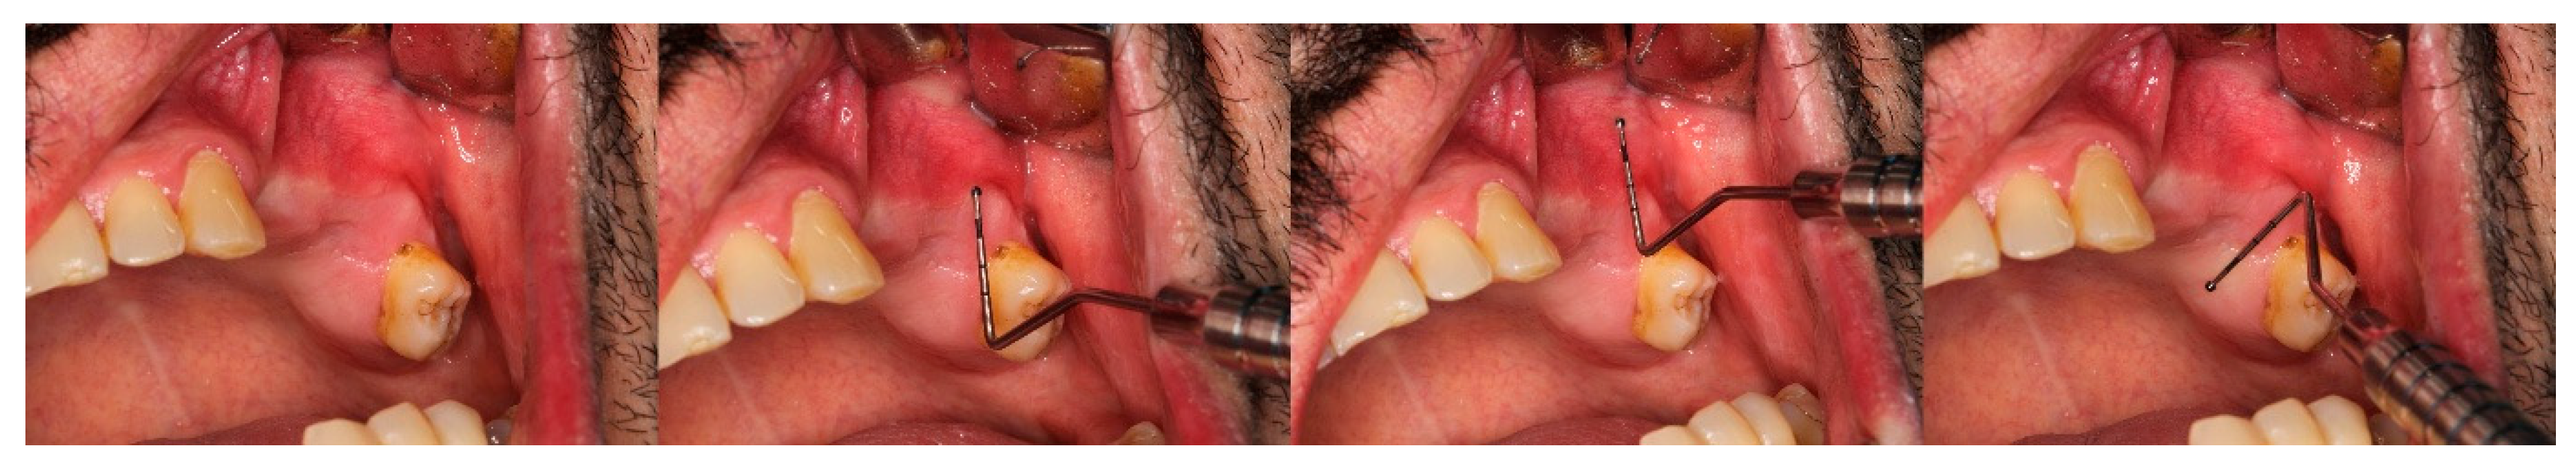

2.10. Pain Assessment

Figure 1. Closure of the oro-sinus connection using a heterogenous membrane.

Figure 2. Measurements of the keratinised gingiva width, vestibular depth, and alveolar socket width on day 0.

Figure 3. Measurement of the keratinised gingiva width, vestibular depth, and alveolar socket width on day 1.